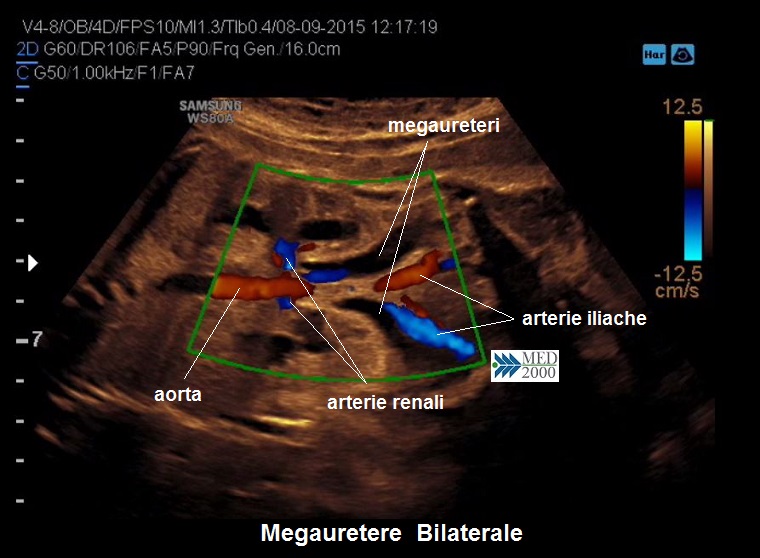

• megauretere: si presenta come una struttura tubulare a decorso rettilineo o tortuoso tra pelvi renale e vescica; il color doppler può aiutare a distinguerlo da strutture vascolari e la continuità con la pelvi renale spesso dilatata lo distinguono dalle anse intestinali. Spesso il megauretere è un segno tardivo per cui il riconoscimento definitivo avviene nel terzo trimestre o alla nascita.

• pielectasia e calicectasia: consiste nella dilatazione della pelvi o bacinetto e dei calici; la diagnosi di pielectasia è effettuata allorquando il diametro antero-posteriore della pelvi è superiore ai 7 mm. Nelle forme severe di pielo-calicectasia si ha compressione del parenchima renale con successiva corticalizzazione.